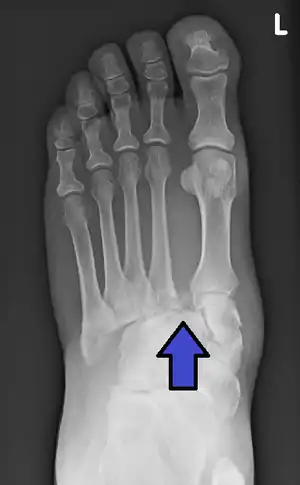

In a high energy injury to the midfoot, such as a fall from a height or a motor vehicle accident, the diagnosis of a Lisfranc injury should, in theory at least, pose less of a challenge. There will be deformity of the midfoot and X-ray abnormalities should be obvious. Further, the nature of the injury will create heightened clinical suspicion and there may even be disruption of the overlying skin and compromise of the blood supply. Typical X-ray findings would include a gap between the base of the first and second toes.[8] The diagnosis becomes more challenging in the case of low energy incidents, such as might occur with a twisting injury on the racquetball court, or when an American Football lineman is forced back upon a foot that is already in a fully plantar flexed position. Then, there may only be complaint of inability to bear weight and some mild swelling of the forefoot or midfoot. Bruising of the arch has been described as diagnostic in these circumstances but may well be absent.[9] Typically, conventional radiography of the foot is utilized with standard non-weight bearing views, supplemented by weight bearing views which may demonstrate widening of the interval between the first and second toes, if the initial views fail to show abnormality. Unfortunately, radiographs in such circumstances have a sensitivity of 50% when non-weight bearing and 85% when weight bearing, meaning that they will appear normal in 15% of cases where a Lisfranc injury actually exists.[10] In the case of apparently normal x-rays, if clinical suspicion remains, advanced imaging such as magnetic resonance imaging (MRI) or computed tomography (CT scan) is a logical next step.[11]